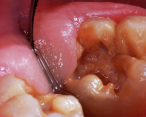

A resin-based composite had failed; the molar was sensitive, malformed, and carious.

Figure 20

A 7-year-old boy originally had resin-based composite repair of his severely malformed permanent molar elsewhere. Chronic tooth sensitivity followed, and the resin-based composite repair failed (Figure 20). The tooth was then restored with a preformed stainless steel crown with careful marginal trimming, crimping, finishing, and polishing, using the methods of Croll and Castaldi (Figure 21 through Figure 23).1,9 The crown is shown 18 months after treatment (Figure 24). This treatment was reported as Case 4 in a prior publication.4 Two years after crown placement, the mesial marginal ridge of the adjacent second molar engaged the distal margin of the stainless steel crown (Figure 25). An orthodontic band was pressed firmly into place over the steel crown, for 3 months, serving to distally reposition the second molar (Figure 26 and Figure 27).